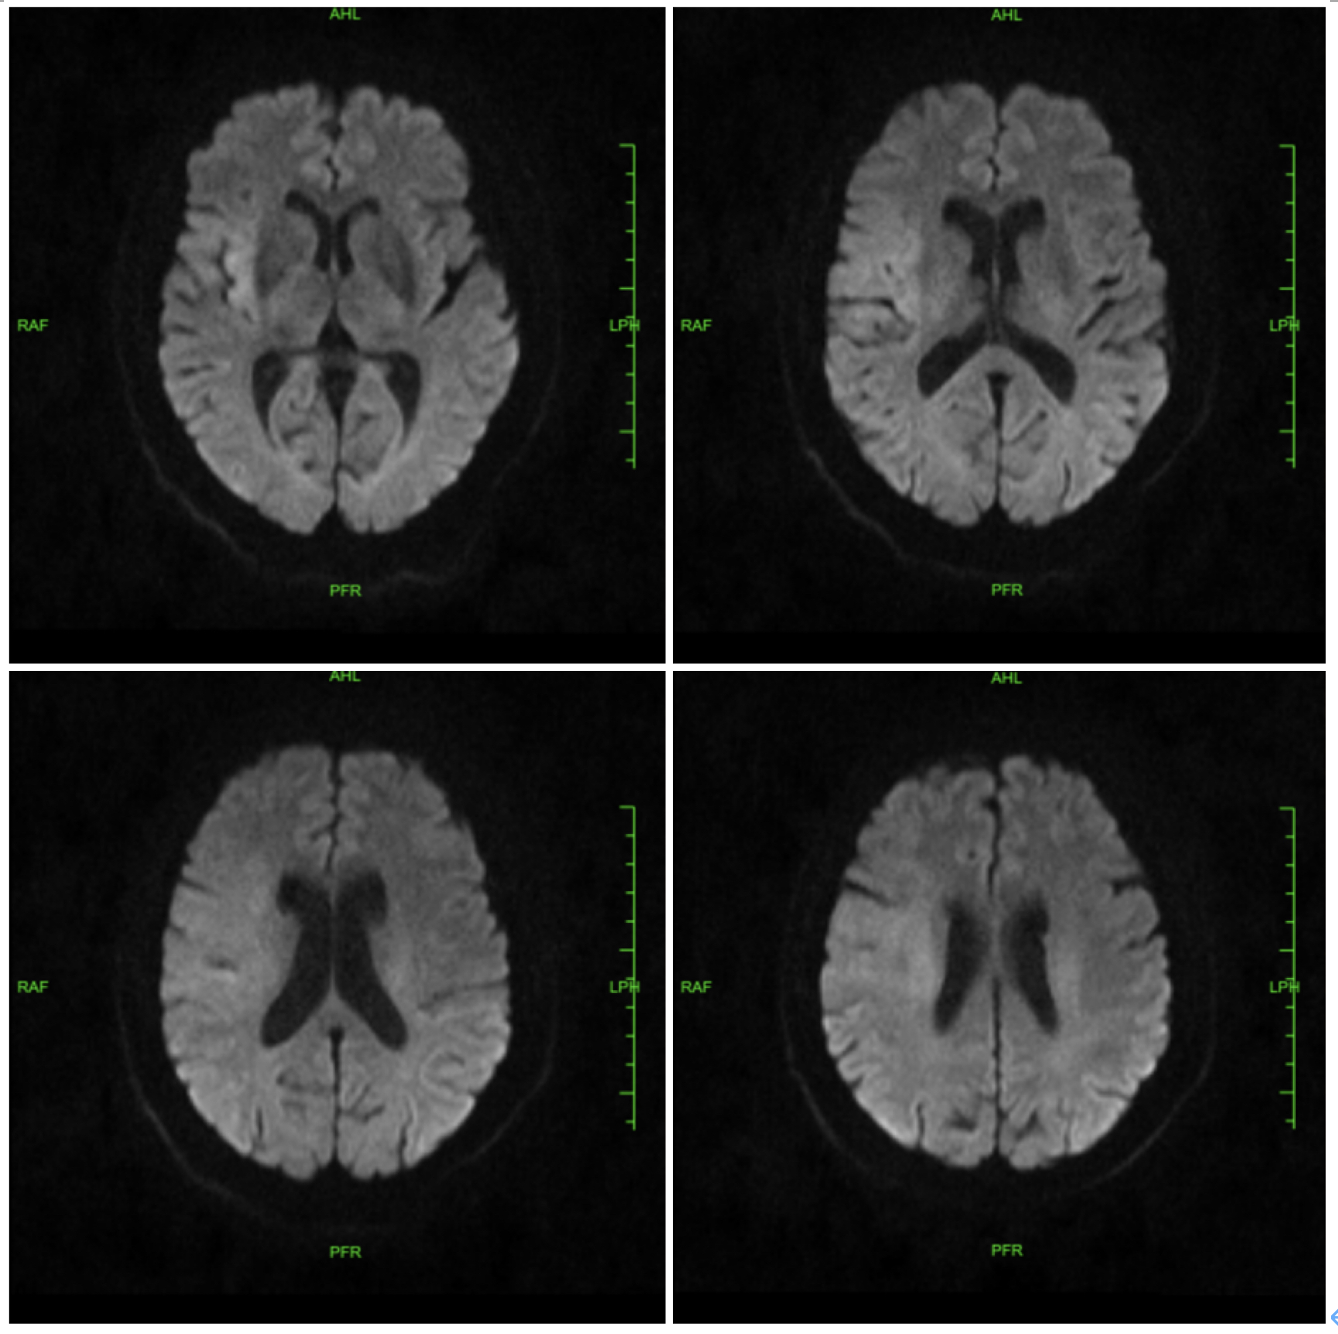

术前影像学检查结果:急诊头颅CT:可见右侧大脑中动脉高密度征,右侧半球未见明显出血及低密度影;头颅DWI:右侧颞叶大面积脑梗死。

简要病史:患者于入院前2小时久坐后突发左侧肢体无力伴失语,双眼向右侧凝视,无意识障碍,急来我院就诊,头颅CT未见出血,头颅DWI提示:右侧颞叶大面积脑梗死,急诊以“急性脑梗死” 收住入院。既往患有高血压20年,口服尼群地平片,一日1片,患有糖尿病20余年,口服二甲双胍缓释片及格列吡嗪控释片治疗,曾有右踝关节手术史。